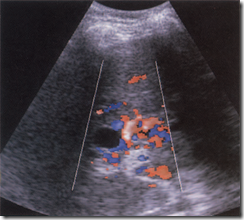

FIG. B Ultrasound images Reversed PV flow in portal hypertension. Note the increased velocity of hepatic arterial flow indicated by the light colour of red just anterior to the portal vein. The patient has macronodular cirrhosis with ascites.

image